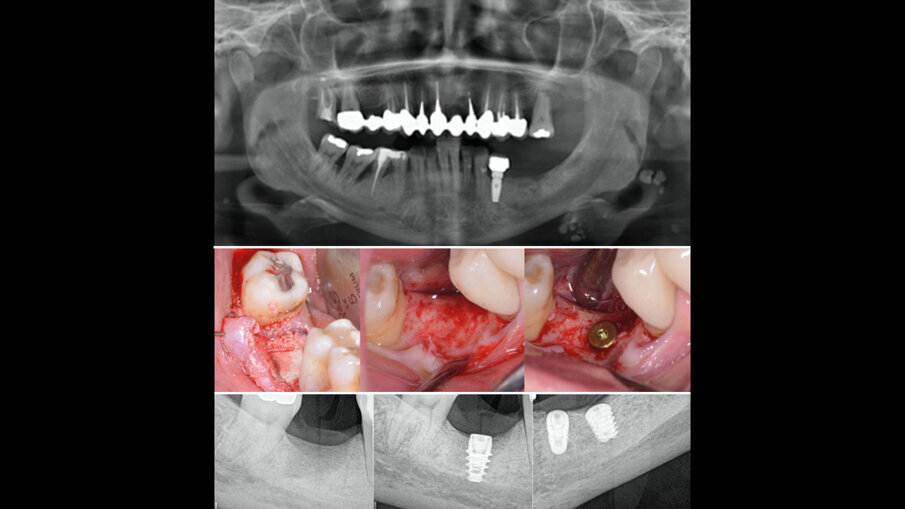

Sulle suture viene applicato l’olio di oliva evo ozonizzato attivato Perioral 3 (Gemavip), che unisce l’efficacia terapeutica dell’olio di oliva alle molecole attive dell’ozono. Grazie a questo processo il prodotto vanta proprietà batteriche, fungicide e antinfiammatorie che svolgono un’azione mirata sulla riparazione epiteliale. Il cetylpyridinium svolge un’azione antisettica e battericida, la clorfenesina è un antimicotico e un miorilassante. Il collagene a basso peso molecolare è facilmente assorbibile e lavora per la rigenerazione cellulare. L’acido ialuronico a basso e alto peso molecolare coadiuva la rigenerazione cellulare. Viene dato alla paziente un bite anteriore di svincolo per riposizionare la mandibola e dopo una settimana viene registrata la posizione delle arcate. Vengono posizionati i nuovi provvisori con le nuove registrazioni occlusali. Nel frattempo vengono inseriti 4 impianti in zona 35, 36, 46 (post estrattivo a carico ritardato con rigenerazione guidata GBR) e in zona 26 a carico ritardato, mentre era già presente un impianto in zona 34 che presentava un minus cervicale con estetica carente (Fig. 7).

Fig. 7 - Inserimento impianti e radiografie di controllo.